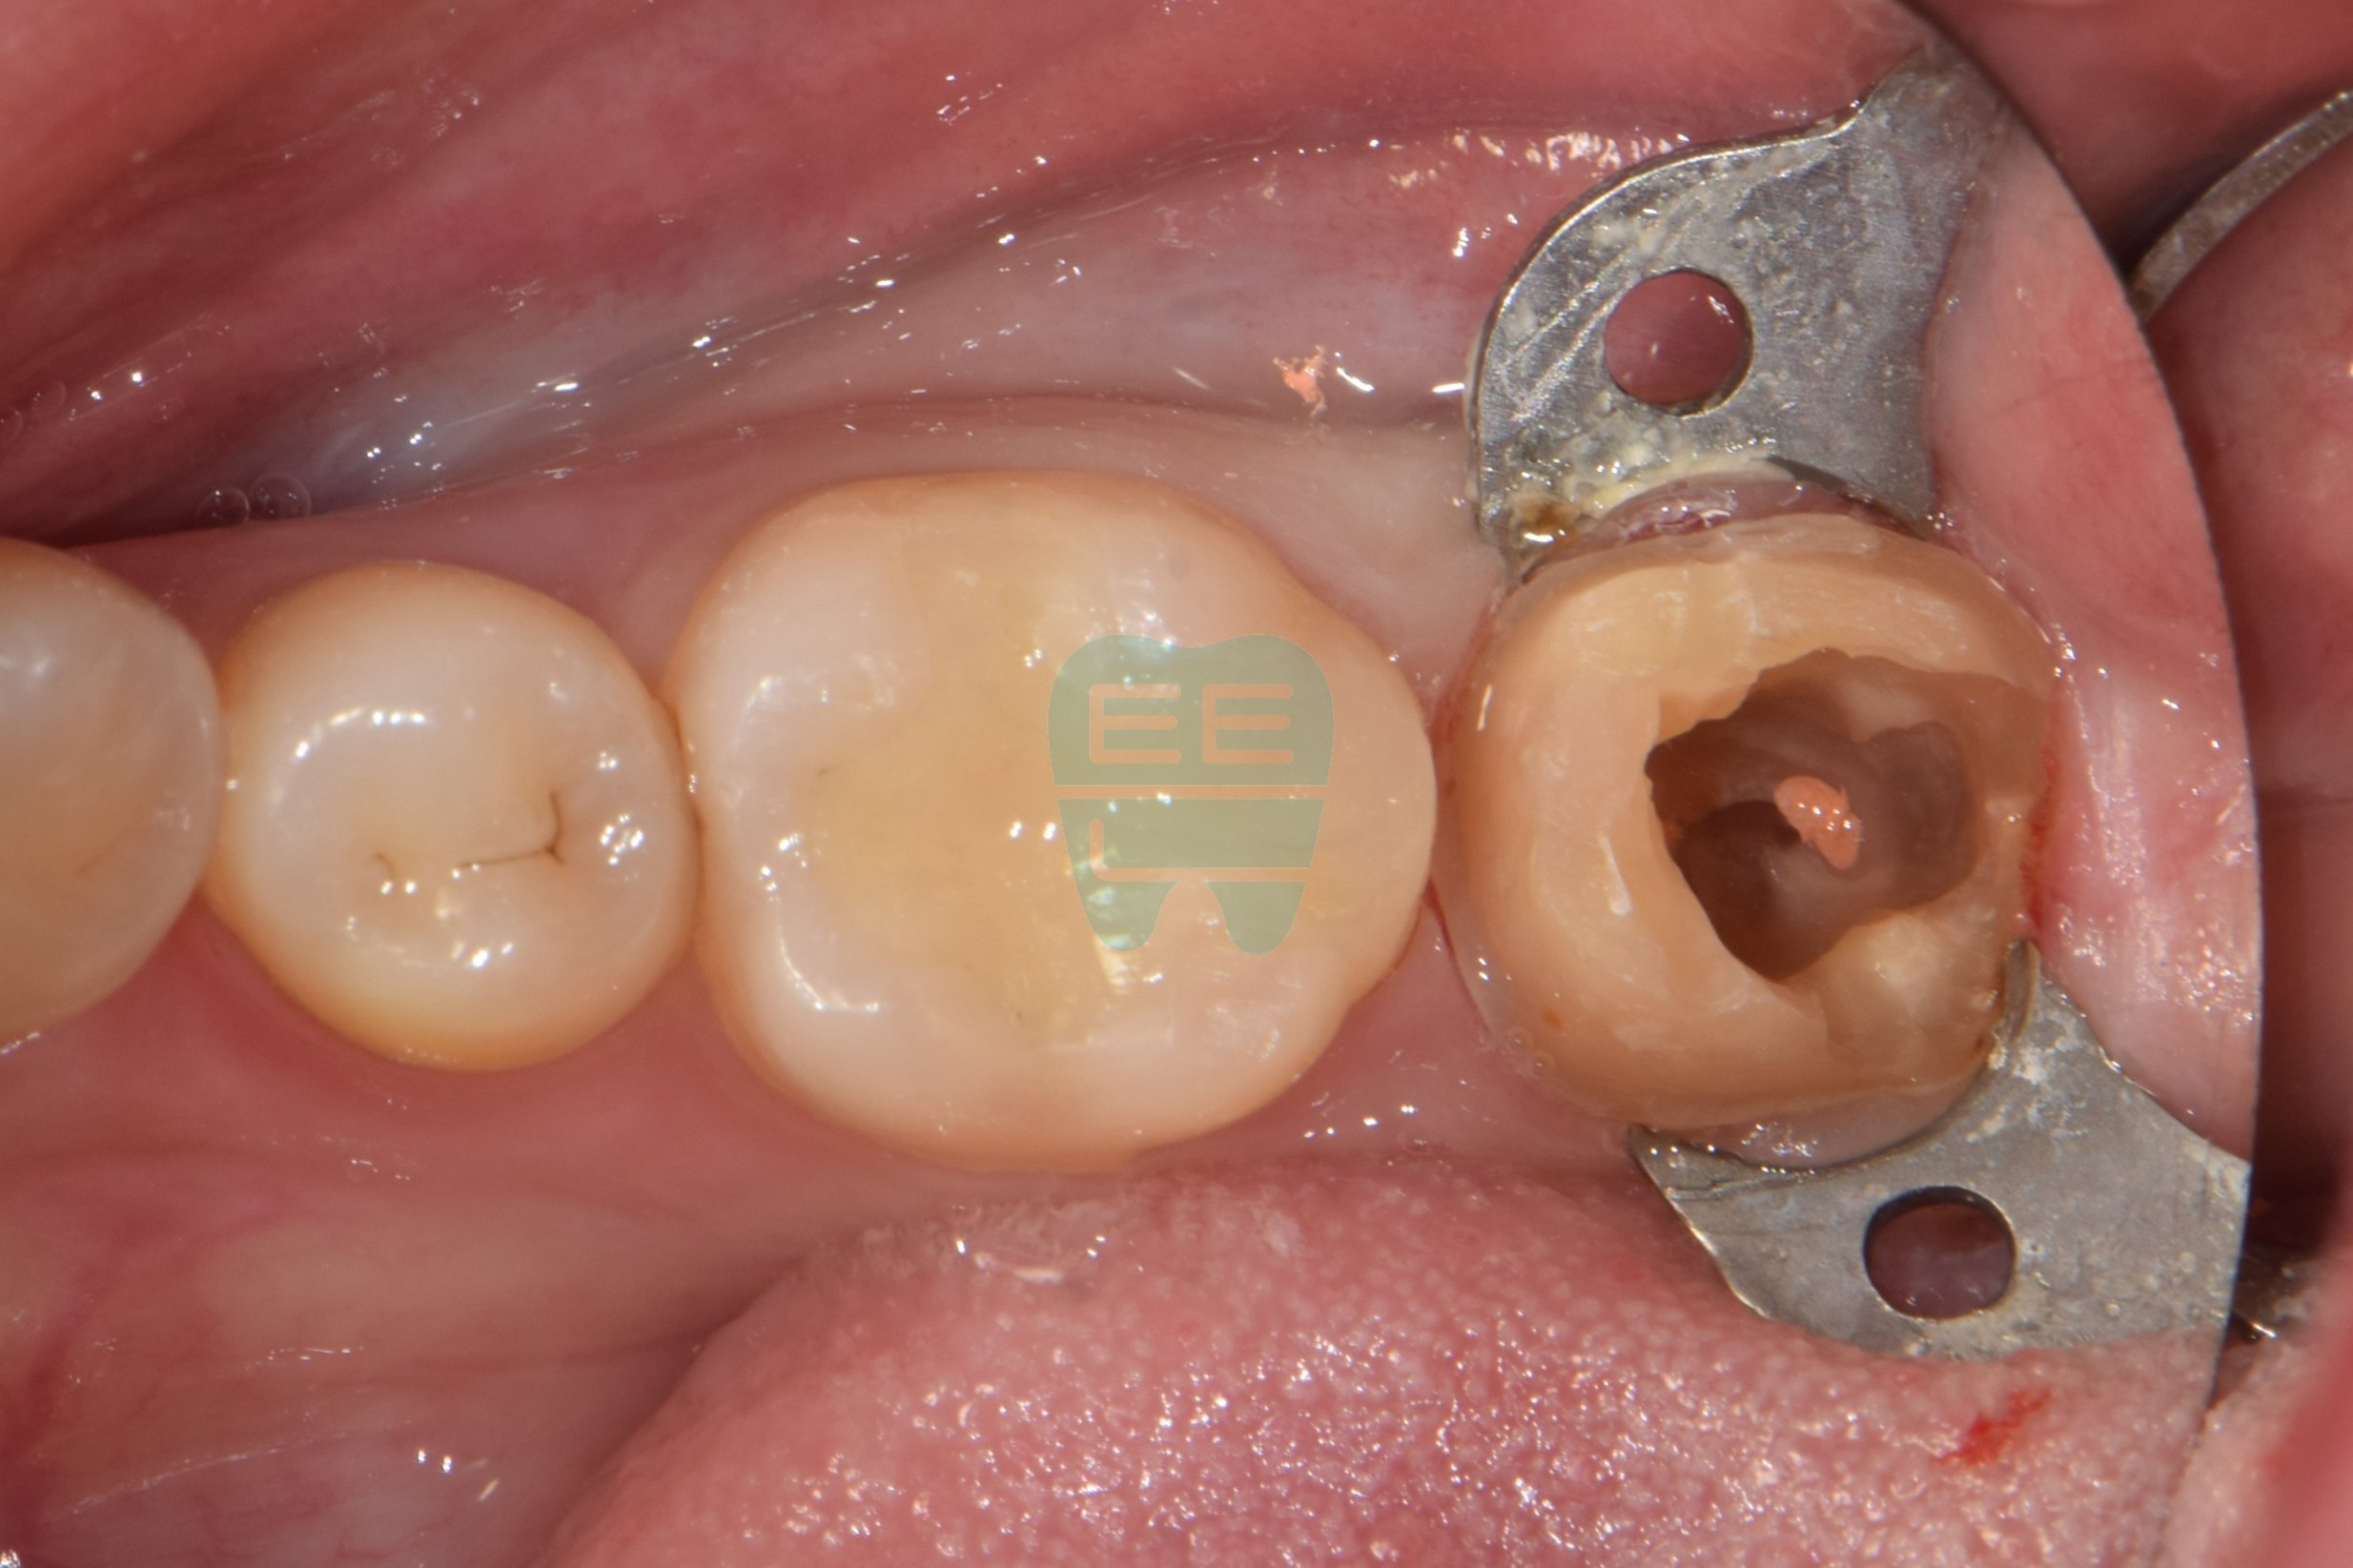

STEP 2. 지르코니아 크라운 제거 후 상태

크라운을 조심스럽게 제거하고 나니, 문제가 바로 눈에 들어왔습니다.

크라운 아래 원심(뒤쪽) 면을 따라 갈색으로 변색된 2차우식이 선명하게 보입니다. 기존 레진코어와 치아 사이의 경계 부위에서 leakage가 발생하여, 그 틈으로 세균이 침투한 것이 냄새의 원인이었습니다.

모든 감염 조직과 기존 레진코어를 제거한 모습입니다. 원심(뒤쪽) 면을 보시면, 치아 벽이 많이 소실되어 잇몸 조직이 안쪽으로 타고 올라와 있는 상태입니다. 이 상태로는 재근관치료를 위한 러버댐 격리도, 새로운 코어 형성도 불가능합니다.

핵심 포인트: 바로 이 상황에서 'wall쌓기'가 필요합니다. 무너진 치아 벽을 레진으로 다시 세워주어야, 러버댐을 걸 수 있고, 러버댐을 걸어야 무균 상태에서 재근관치료를 진행할 수 있습니다.

STEP 4. 러버댐 장착 및 Wall 쌓기

재근관치료의 성공률을 높이기 위한 가장 중요한 단계입니다. 먼저 러버댐(Rubber Dam)을 장착하여 타액과 세균을 완벽하게 차단합니다. 그리고 소실된 원심면 치아 벽을 레진으로 꼼꼼하게 쌓아 올려(Wall Build-up) 밀폐된 환경을 만듭니다.